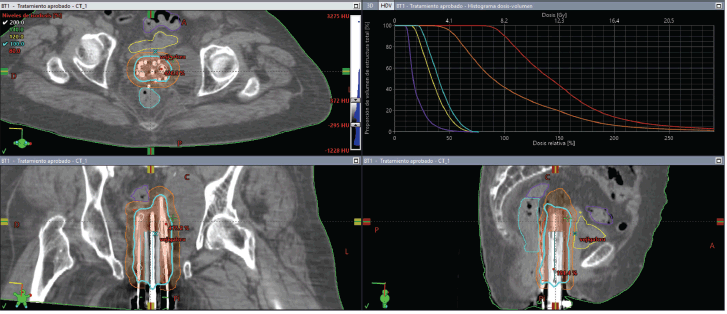

On the day of implant, the patient underwent spinal anesthesia, and a Foley catheter was placed. The custom template was positioned against the perineum, and 18 interstitial needles were inserted according to the pre-plan. An initial fraction was delivered at 8.2 Gy to the 90% isodose of the GTV (Figure 7). For subsequent fractions, the central channel was exchanged for a deeper needle to cover more cranial disease.

Figure 7. Case 2. Dose-volume histogram and dosimetric distribution of fraction #1 in axial, coronal and sagittal planes. It is shown in red CTV-HR, in orange CTV-IR, in light blue the rectum, in yellow the bladder and in purple the sigmoid colon.

Total dose was 8.2 Gy × 3 fractions, equating to roughly 48.1 Gy EQD24.5. The plan accounted for prior EBRT (30 Gy in 10 fractions). Although the bladder, rectum and sigmoid colon had some overlap with the new target volume, no dose-limiting constraints were exceeded (Table 1).